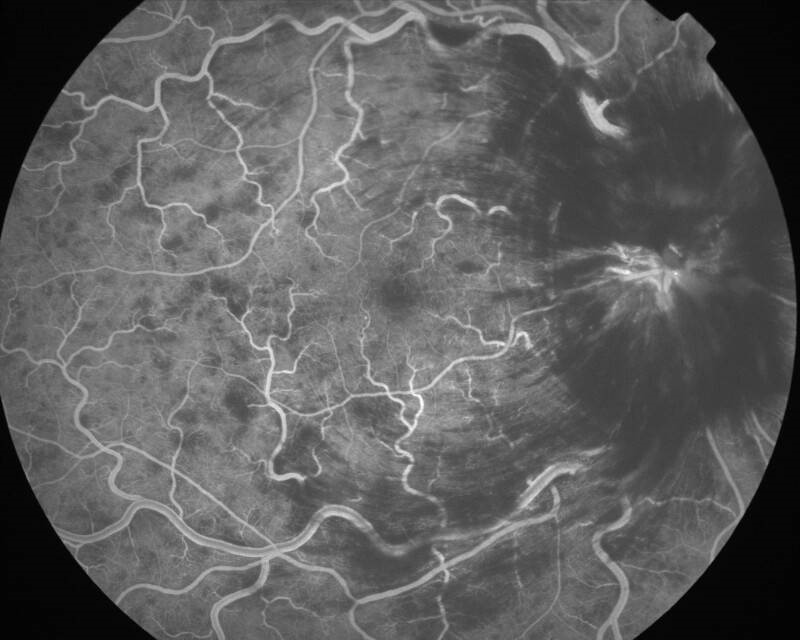

Une patiente de 75 ans arrive aux urgences ophtalmologiques pour sensation de baisse d’acuité visuelle brutale de l’œil droit depuis le matin au réveil.

Elle décrit également une ondulation des lignes à la lecture.

Son œil droit est blanc et indolore. On retrouve une acuité visuelle chiffrée à moins de 0,5/10e à droite contre 8/10e à gauche. Il n’y a pas de notion de traumatisme.

– un diabète de type 2 non insulino-dépendant traité par metformine depuis plus de 15 ans, avec HbA1c à 7 % ;

– une arythmie cardiaque par fibrillation auriculaire (ACFA) avec antécédent embolique, sous anticoagulation efficace.